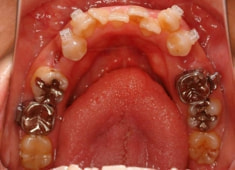

治療開始時